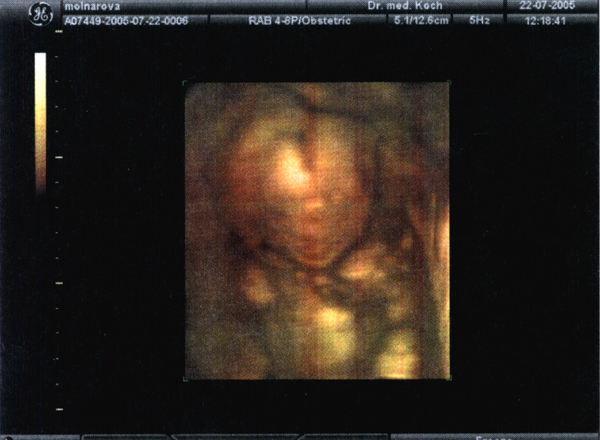

22.07.05 - 20. Woche - 22,0cm